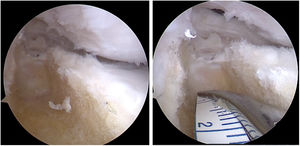

Sin embargo, el dolor y molestias no ceden a los dos meses posteriores a intervención quirúrgica, por lo que se realiza menisectomía subtotal artroscópica (fig. 1) sin conseguir mejoría de síntomas.

TécnicaBajo anestesia general y uso de torniquete, se realiza abordajes artroscópicos antero lateral y antero medial, se localiza abordaje postero-lateral, tomando como referencia anatómica intraarticular, el tendón poplíteo, y abordaje anterior externo longitudinal de 3cm aproximadamente a nivel de meseta tibial externa, realizando canal óseo de forma trapezoidal, donde se coloca el aloinjerto cadavérico con bloque óseo previamente preparado para encaje a presión y se fija con tornillo canulado de 4.0mm desde superior a inferior en ángulo oblicuo sin afectar a la fisis, corroborando con equipo de fluoroscopía, finalmente se sujeta el menisco mediante fijación periférica hacia la cápsula (figs. 2-6).